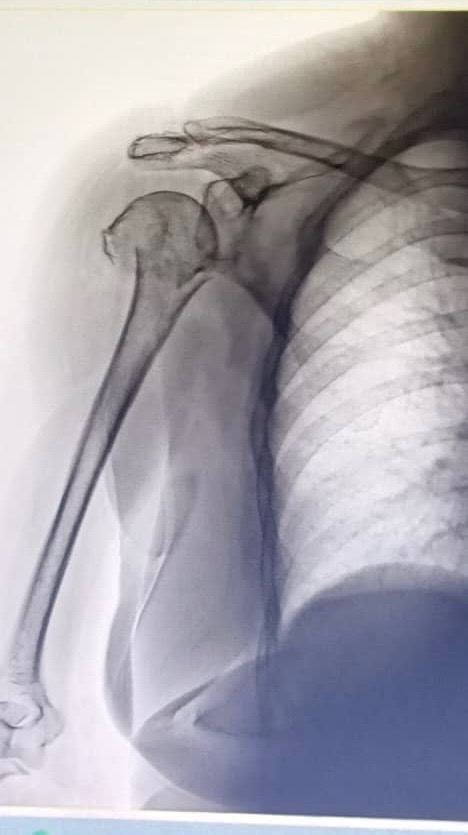

Last week, Mima fell and fractured her proximal humerus (upper arm and shoulder). The injury is severe, and surgery is now medically necessary to restore her mobility and relieve her pain.